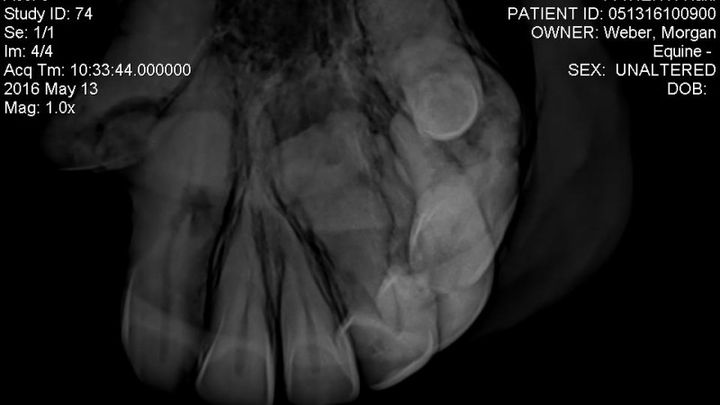

Those who know me well also have had the pleasure of meeting my life long best friend, Harli. He is a pure Spanish Arabian who just turned 26 on Friday the 13th. We have been by each others sides for 16 years - since I was 12! On his birthday Harli had X-rays done on his front teeth because the Vet suspected he had EOTRH *For more detailed info on the disease, see website : http://www.midwestequineservices.com/eotrh-syndrome/

Having done full blood panels and testing for other disorders and diseases to have them all come back negative, with X-ray images such as the one provided, it is clear now that this dental disease, which has gone undetected in Harli for what appears to be many years now, is the cause of his dramatic weight loss and inability to gain weight.

Unfortunately he has a very serious case of this dental disease newly identified in the equine world. Not much is known as to the cause nor the preventative treatment, but once a horse has it all that can be done is to remove the teeth entirely. Harli needs most if not all of his front teeth surgically removed at a surgical facility in Gilroy, CA so that his chronic pain can end.